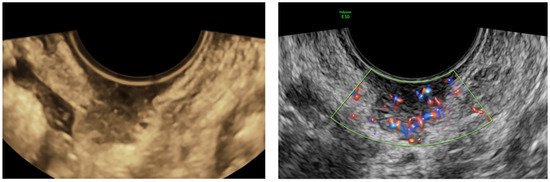

| Site of access (N, %) | |

| Transvaginal | 31 (73.8%) |

| Transabdominal | 11 (26.2%) |

| Site of biopsy (N, %) | |

| Lesion | 34 (81%) |

| Omental cake | 4 (10%) |

| Carcinosis | 4 (10%) |